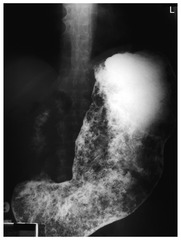

enlarged tortuous veins of lower esophagus resulting from portal hypertension

esophageal varices

Back